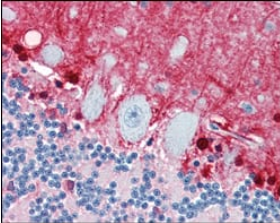

S100B Mouse Monoclonal antibody[9A11B]

IHC    1/200 - 1/1000